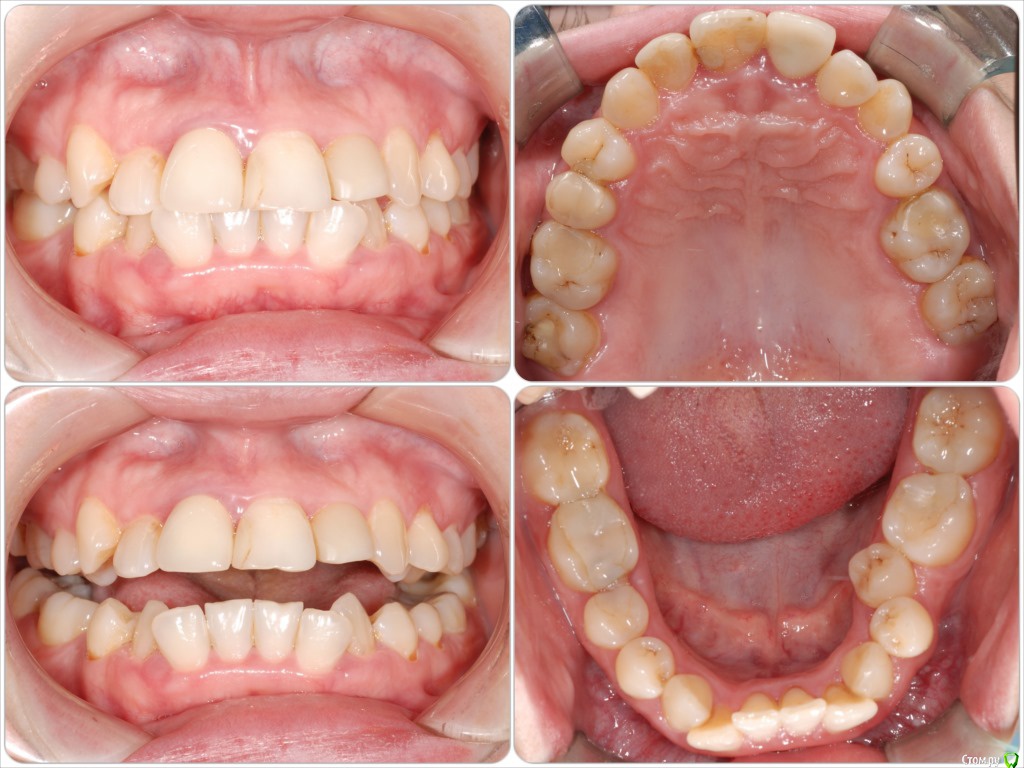

Galaola Опубликовано 28 февраля, 2016 Поделиться Опубликовано 28 февраля, 2016 Добрый день! Мне 36лет. Удалена правая верхняя 4 в детстве. При выборе ортодонта остановилась на варианте без удаления зубов, но с сепарацией зубов НЧ. Через 6 мес лечения ортодонт заявляет об удалении правой нижней 8 как минимум, а лучше всех. Прошу совета и мнения специалистов. Насколько необходимо удаление 8-к? Возможно ли расширить ВЧ и каким образом? Возможно ли подготовить место под имплант отсутствующей 4 или поставить адгезионный мост? Спасибо. Ссылка на комментарий

Galaola Опубликовано 1 марта, 2016 Автор Поделиться Опубликовано 1 марта, 2016 Возможно ли расширить ВЧ и каким образом? Возможно ли подготовить место под имплант отсутствующей 4 или поставить адгезионный мост? без расчетов можно это определить? Ссылка на комментарий

Yana guapa Опубликовано 2 марта, 2016 Поделиться Опубликовано 2 марта, 2016 без расчетов можно это определить? расчеты ортодонтические каждый врач делает для себя свои, те, которые ему нужны и удобны в работе ортодонтические, для имплантаций.. расчет для имплантации делает врач- имплантолог после того, как ортодонт создаст место для импланта (если создаст))) Ссылка на комментарий